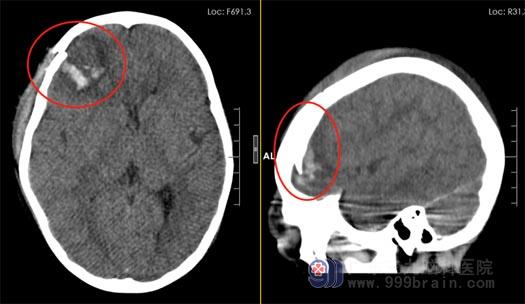

回忆起事故发生的那天:林林跟弟弟在一楼玩,不知何时林林独自一人上到了二楼,随着“砰”的一声响后,爸爸先发现了昏迷在地上的孩子,立马抱起林林往医院飞奔。头颅CT示右额叶开放性脑挫伤;右侧额颞骨开放性骨折;右侧额部硬膜下血肿 头皮裂伤。病情危急!当地医院建议立即转上级医疗机构。

▲术前